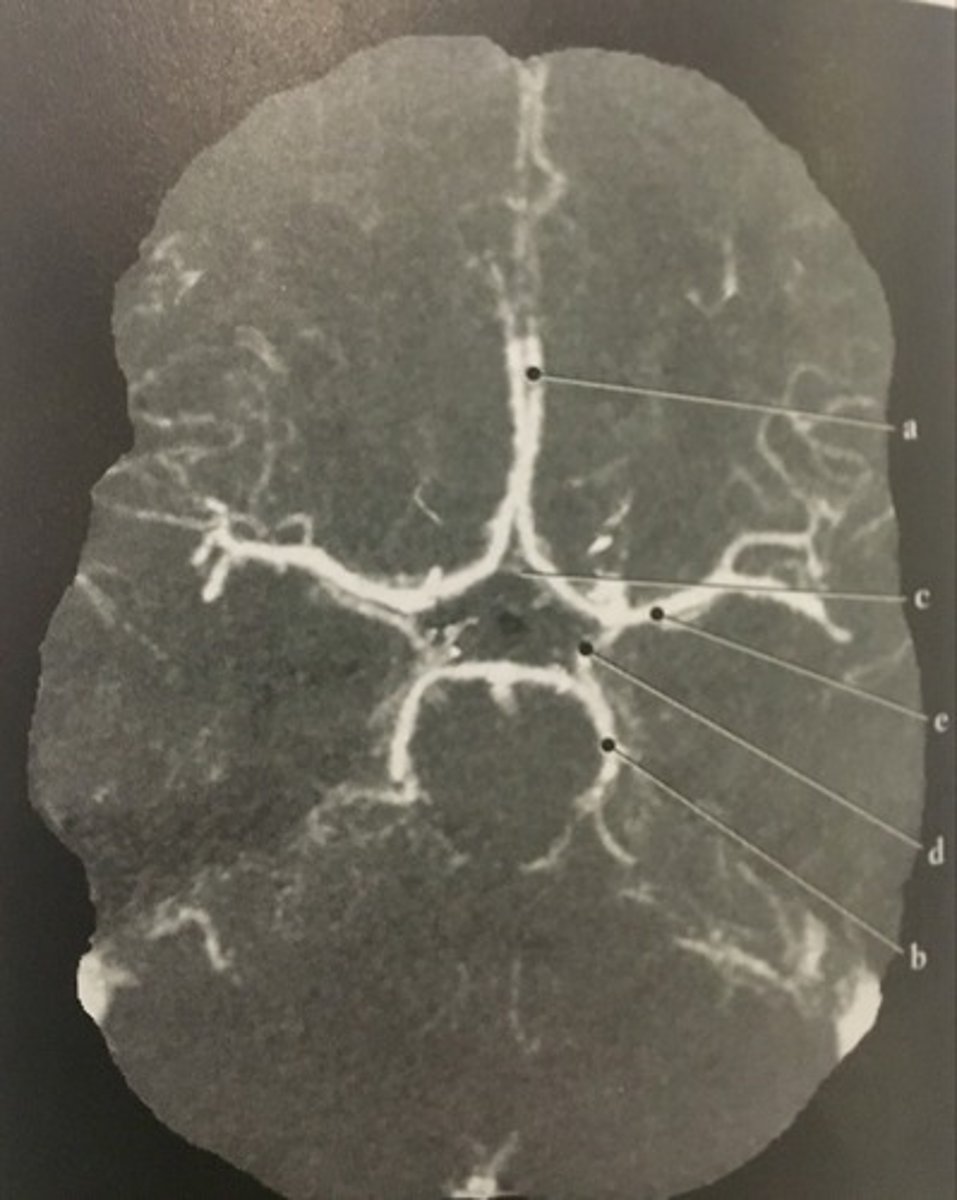

Stomach

Number 1 corresponds to which of the following?

<p>Number 1 corresponds to which of the following?</p>

13

New cards

Anterior cerebral artery

Identify structure A on this axial CTA of the Circle of Willis.

<p>Identify structure A on this axial CTA of the Circle of Willis.</p>

86

Posterior cerebral artery

Identify structure B on this axial CTA of the Circle of Willis.

<p>Identify structure B on this axial CTA of the Circle of Willis.</p>

87

Anterior communicating artery

Identify structure C on this axial CTA of the Circle of Willis.

<p>Identify structure C on this axial CTA of the Circle of Willis.</p>

88

Posterior communicating artery

Identify structure D on this axial CTA of the Circle of Willis.

<p>Identify structure D on this axial CTA of the Circle of Willis.</p>

89

Middle cerebral artery

Identify structure E on this axial CTA of the Circle of Willis.

<p>Identify structure E on this axial CTA of the Circle of Willis.</p>